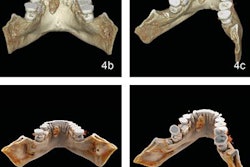

The researchers took images of 110 human premolars with 120 root canals. They used the VistaScan digital intraoral system (Durr Dental) for the periapical radiographic images and the 3D Accuitomo CBCT unit (J. Morita) for the CBCT images. They also took images of the canals with a micro-CT system to serve as the gold standard for the study.

Apical deltas were present in 40 root canals according to the micro-CT images, the researchers reported. They found that the periapical radiographs and CBCT images differed significantly from the gold standard (p < 0.05) in detecting apical deltas (see table below).